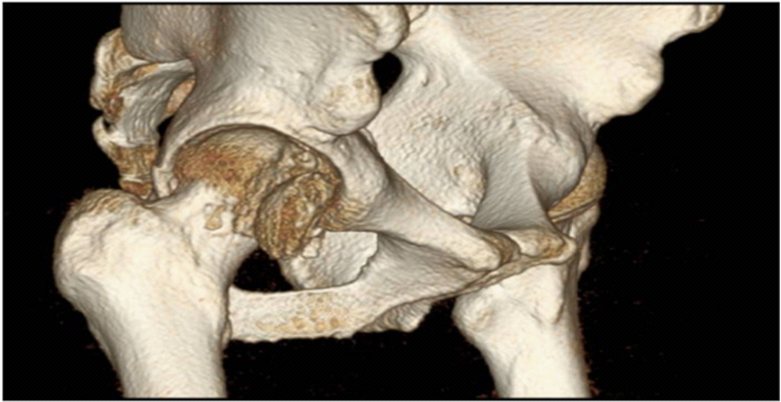

A 27-year-old man was injured by automobile accident and immediately presented to our emergency department. On physical examination, right hip was in flexion, external rotation and abduction. He complained of severe pain, and passive and active movements were not possible in right hip. There was neither neurovascular deficiency nor associated injuries. Radiograph of both hip revealed obturator dislocation of right femoral head and fractured femoral head fragment within hip joint (Figure 1). The dislocation was immediately reduced by traction in line of deformity followed by gentle adduction and internal rotation with pelvis stabilized by an assistant. After closed reduction, anteroposterior radiograph showed femoral head was reduced but crescentic radio-opacity was visible overlying femoral head and translateral radiograph revealed that the fractured femoral head fragment was turned inside out during closed reduction (Figure 2A & 2B). Computed tomogram depicted the 3-D configuration of fracture (Figure 2C & 2D).